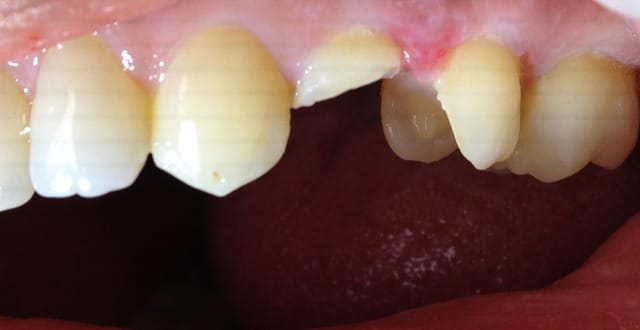

Voici les photos toutes fraiches de ce matin.

Vos critiques sont bien sur les bienvenues je dois encore beaucoup m'améliorer sur les prises de teintes, et je m'y attelle en ce moment,, par contre en ce qui concerne la pérennité de la restauration…..ma patiente a sa dent bien vivante, aucun joint sous gingival , possibilité de réaliser une endo dans le futur sans détruire la restauration existante si besoin, possibilité re refaire un onlay dans quelques années si ça casse, toujours sur dent vivante…. bref la liste des avantages est très longue par rapport au classique endo-IC-CCM.